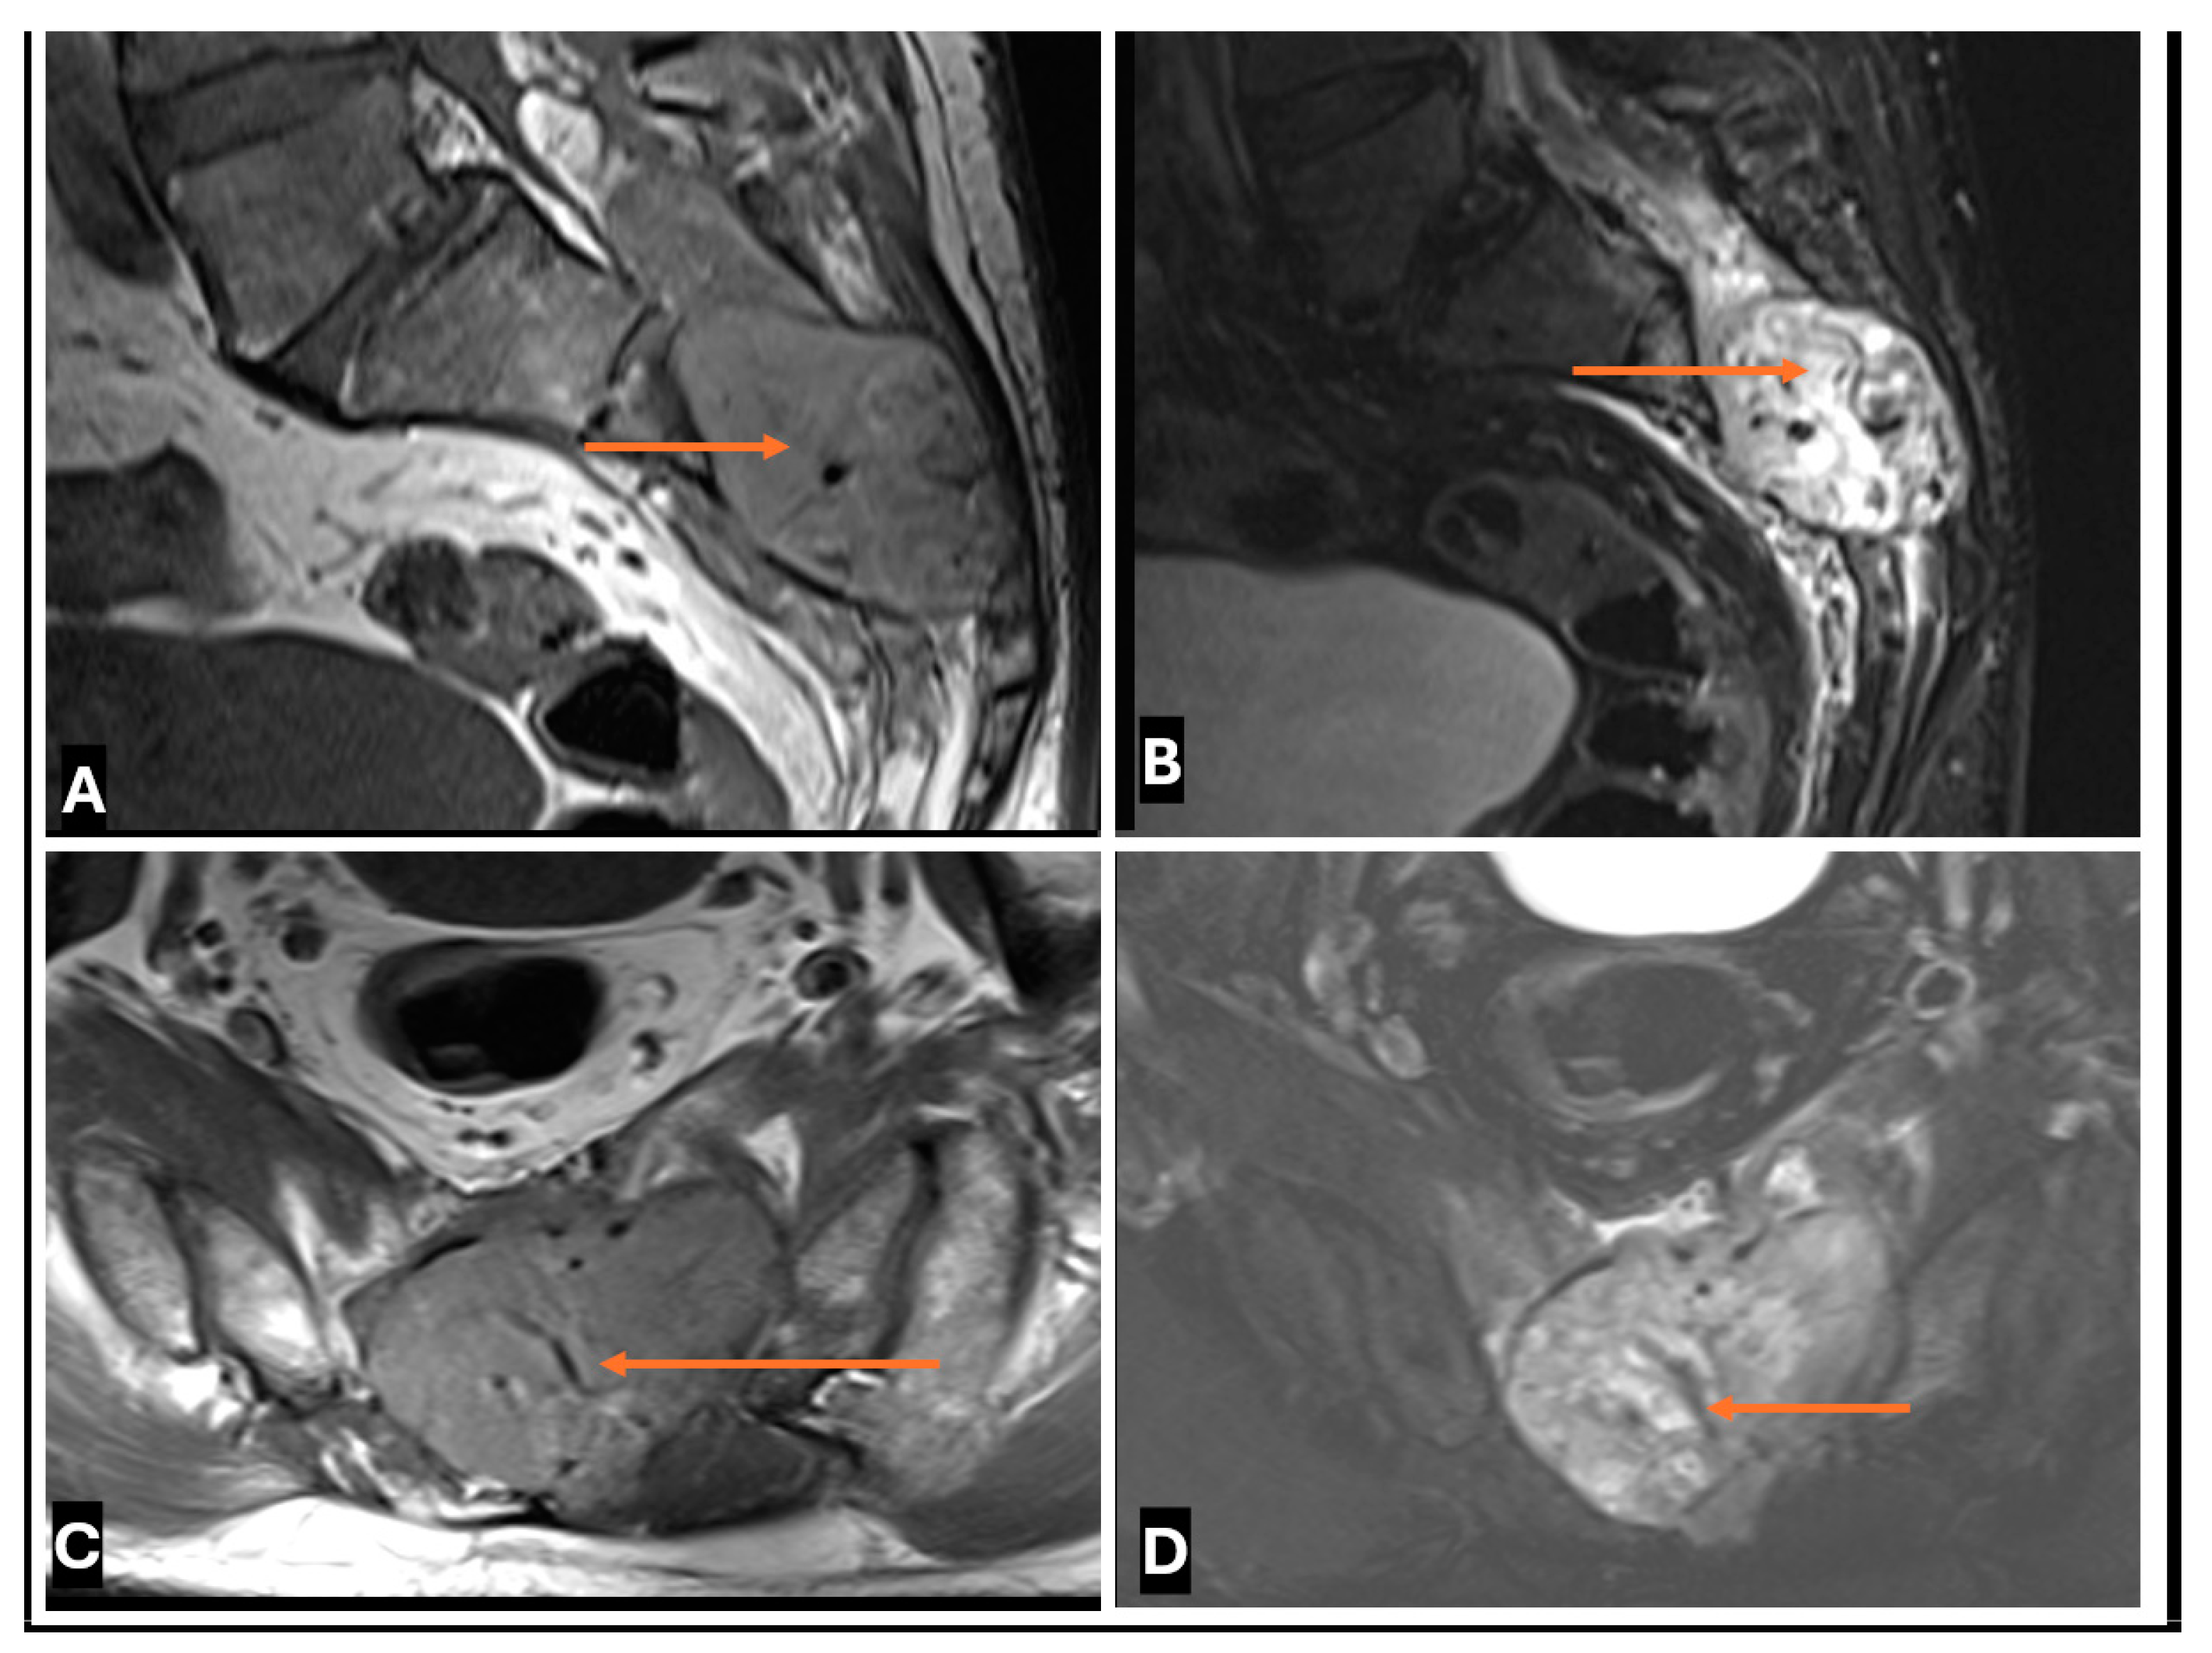

- Neurolymphomatosis describes intraneural spread of lymphoma and appears as diffuse enlargement of nerves, plexuses, spinal cord, and cauda equina. It shows more homogeneous enhancement than PNSTs and may be associated with lymphadenopathy or a known history of lymphoma [63] (Figure 20 and Figure 21).